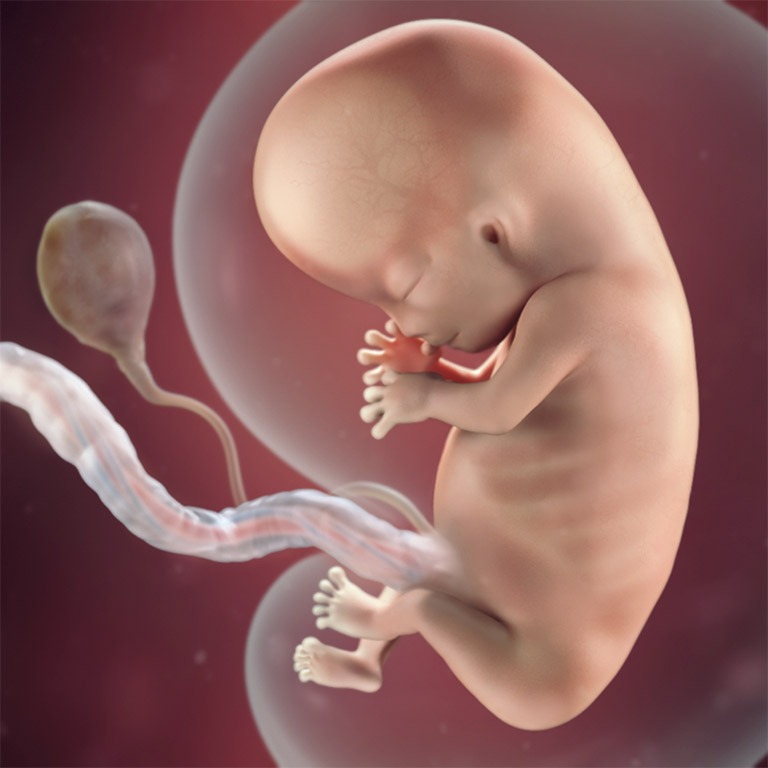

Trong suốt quá trình mang thai, chiều dài xương mũi là một trong những yếu tố được xác định để đưa ra đánh giá về sự phát triển của thai nhi. Xương mũi cũng là một trong những cấu trúc được xem xét cẩn thận trong hình ảnh siêu âm. Chiều dài xương mũi thường được sử dụng như một chỉ số để ước lượng tuổi thai nhi và đánh giá sự phát triển của hệ thống xương khuôn mặt.

Như vậy có thể thấy việc đo chiều dài xương mũi không chỉ giúp dự đoán tuổi thai nhi mà còn đóng vai trò quan trọng trong việc theo dõi sự phát triển chi tiết của cả hệ thống xương và kết cấu khuôn mặt. Đây là một công cụ quan trọng để các bác sĩ đưa ra đánh giá chính xác và phát hiện sớm mọi yếu tố có thể ảnh hưởng đến sức khỏe của thai nhi.